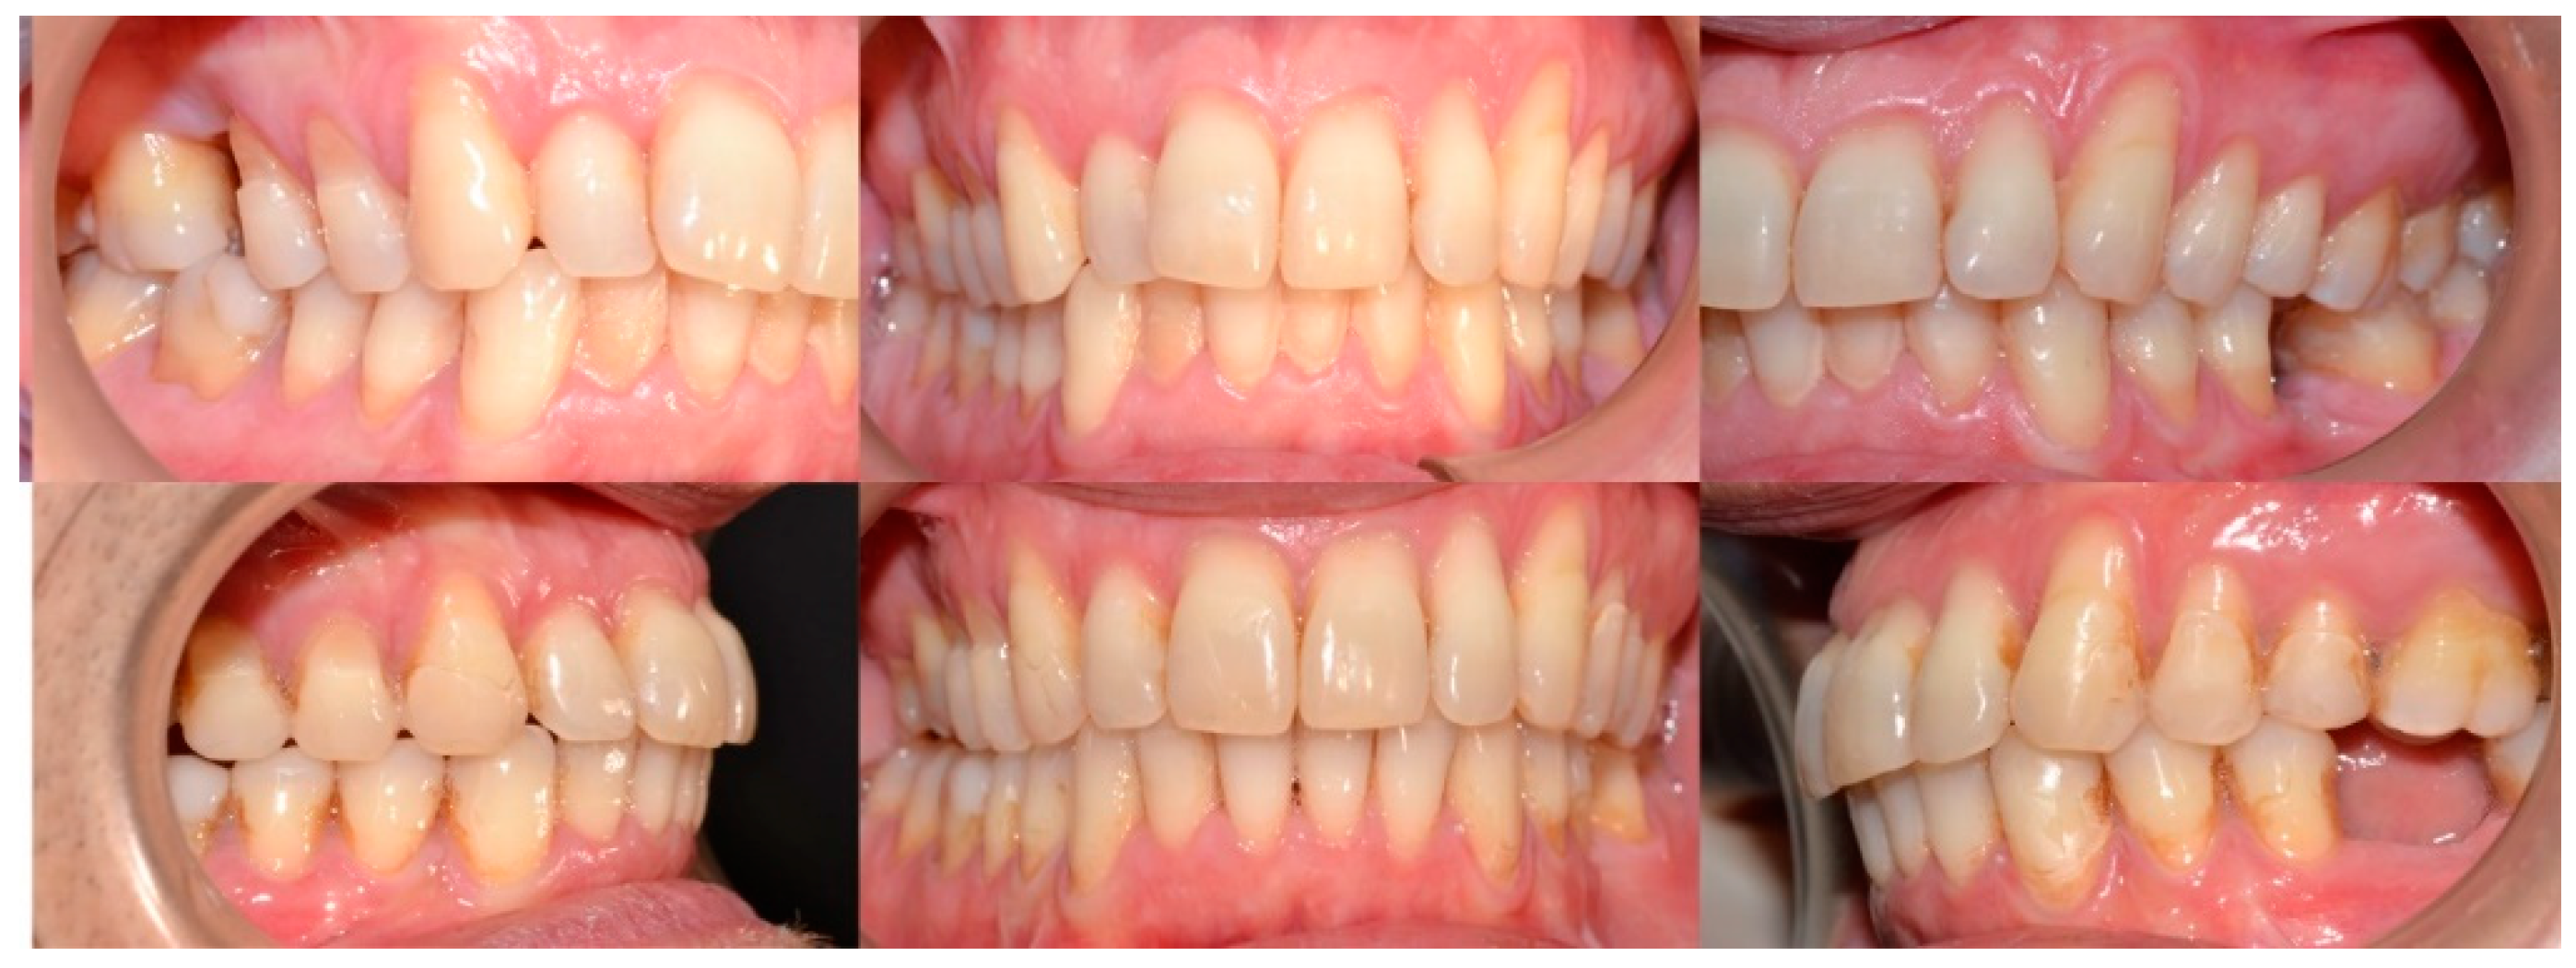

2.3.1. Example—Anterior Open-bite

2.3.2. Example 2—Extraction Space Closure